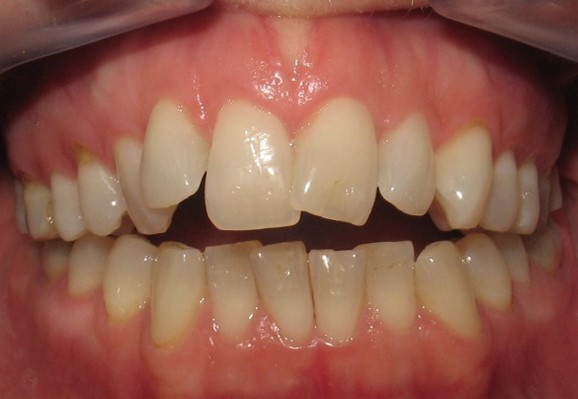

図A. 舌突出による前頭咬合の開き具合が異なる2つの症例

図B. 患者は右側顎関節の変形性関節症/骨欠損により右側のみに咬合接触がある。